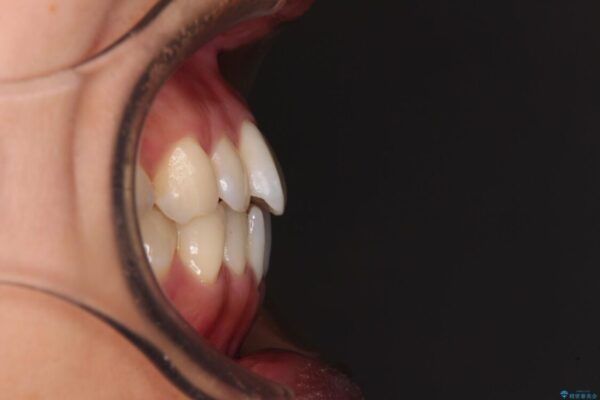

前歯のデコボコで前方に出ていることを気にして来院された患者様です。

上顎前歯が捻れて前方に飛び出しており、下顎前歯もそれに沿うようにデコボコとなっていました。

IPR(歯と歯の間を削る処置)によりスペースを獲得して上下顎前歯のデコボコを改善し、飛び出している前歯が引っ込むように設定し、インビザラインにて矯正治療を行うこととしました。

• 【モニター】前歯のデコボコをインビザラインで改善 治療前画像